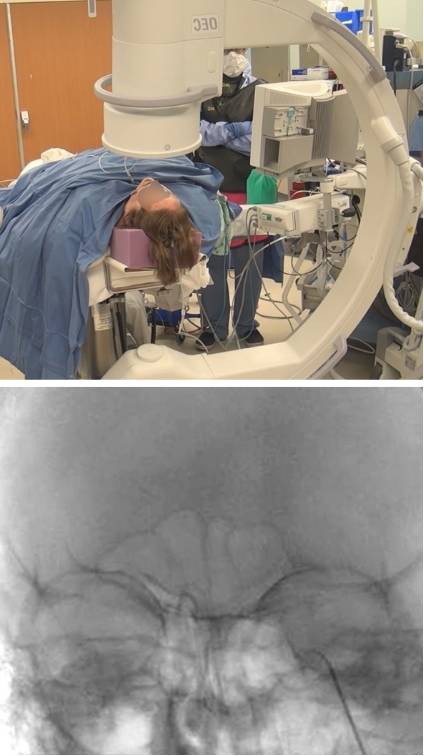

图2. 手术室的布局,发生器位于后方。X光机的显示器正对着术者。

图4. 改良的前后经眶位图像(上图)从另一个角度确认射频点极头位置是否正确。X光机光束角度要调整到岩骨嵴位于眼眶中部。射频电极插入三叉神经半月节的中间部分,电极头位于岩骨嵴边缘(下图)。